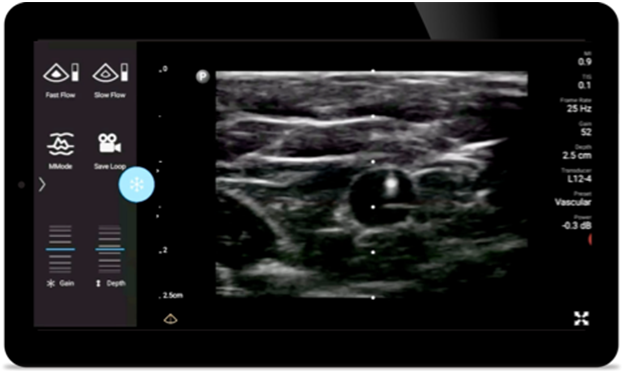

Improve precise placement on visually defined nerve blocks, so you can get in and out faster. And perform quick and thorough post-operative follow ups.

Reduce complications

in needle guided procedures

Lumify handheld ultrasound for anesthesiology helps you clearly visualize border definition with your needle placement, surrounding nerves, vessels and fascial planes.

Lumify helps you clearly visualize needle placement, surrounding nerves, vessels and fascial planes.